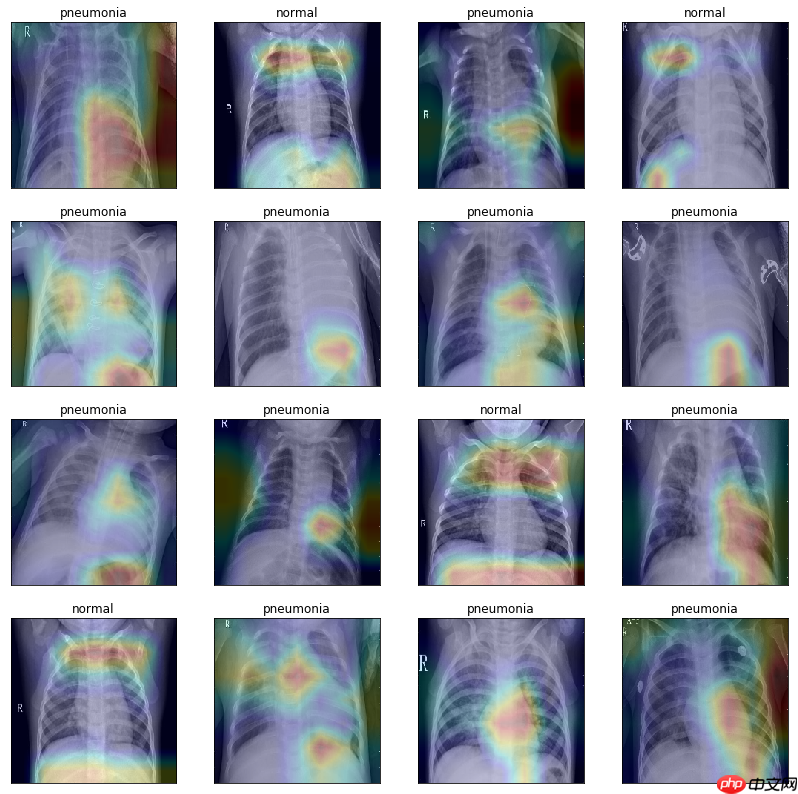

根据大佬FutureSI提到Grad-CAM 梯度加权的类激活热图原理中,需要获取网络最后一个卷积层输出的特征图,然后计算它的梯度。所以网络设计的时候需要提供一个方法,用来获取最后一个卷积层的输出

row = 4fig = plt.figure(figsize=(14,14))for idx in range(num):

ax = fig.add_subplot(row,int(num/row), idx+1, xticks=[], yticks=[])

image = paddle.unsqueeze(images[idx], axis=0)

heat_map = show_gradcam(model, image, labels[idx], class_dim=2)

heat_map = cv2.cvtColor(heat_map, cv2.COLOR_BGR2RGB)

plt.imshow(heat_map) if labels[idx]:

ax.set_title('pneumonia') else:

ax.set_title('normal')/opt/conda/envs/python35-paddle120-env/lib/python3.7/site-packages/paddle/fluid/dygraph/varbase_patch_methods.py:373: UserWarning: Warning: tensor.grad will return the tensor value of the gradient. warnings.warn(warning_msg)

<Figure size 1008x1008 with 16 Axes>